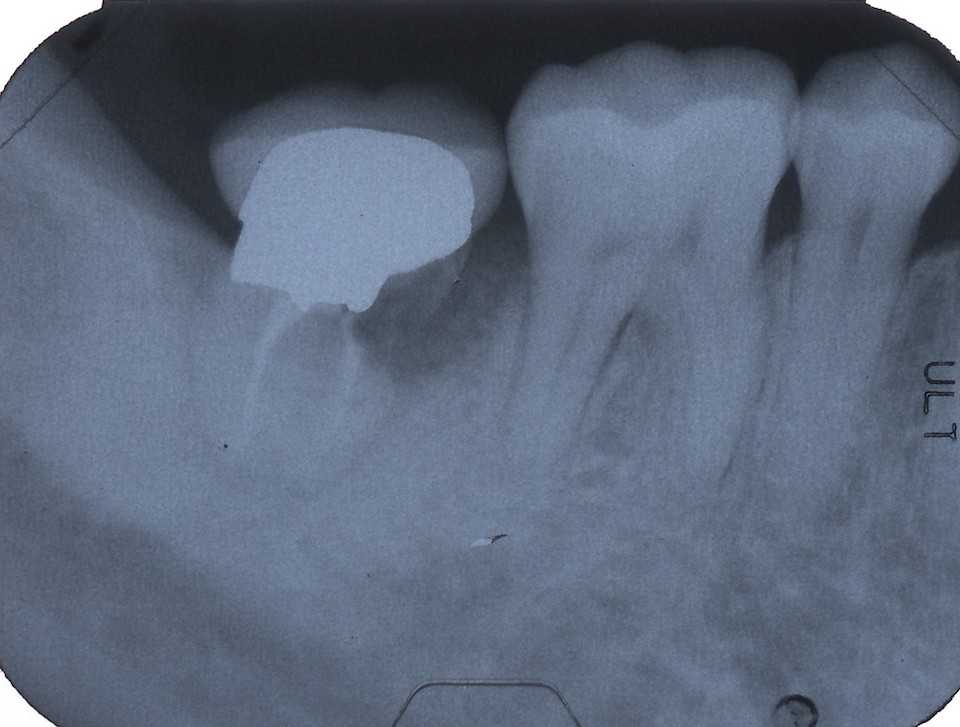

30代女性、右下7、Per、歯牙破折、歯根吸収?ほとんど抜けそうな(抜けている)状態で来られた。ご本人にお訊きしてもどうしてこうなったのか記憶にないそうだ。とりあえずレントゲン写真でのbefore/afterだが、近心の歯根が半分無くなっている。吸収されたのか、破折して破折片がどこかに行ってしまったのか、よく分からない。とりあえず抜いてみるしかない。beforeafter処置前はセラミック系の冠が装着されていたが、グラグラしている。冠は横から切断して除去した。歯根は前後(近遠心的)に破断していてグラグラしているのを確認した。どこまで健全歯質が残っているか軟化象牙質を削除しながら見てみたが、切削バーが届く範囲で健全歯質を確保するのはできなかった。抜歯してみないと正確なところは分からない。抜歯して直視下で見ないと軟化象牙質を除去し、健全歯質を出すことはできない。健全歯質の新鮮面を出さないとスーパーボンドは接着しないので、歯根の再建はできないということになる。抜歯再植は次回にすることにしてα-TCPで仮封鎖した。つづく

40台女性、左下6、Per、外傷性クラックGAができていたので歯髄を開けて見たのだが、クラックがあったので3MIX+α-TCPで根管充填したが、GAは消えなかった。やはりクラックが深部まで進んでいるのか?これ以上の打つ手がないので抜歯再植を試みた。抜歯も分割抜歯だったがまだ病状が進んでいないので骨植もよかったので、かなり時間もかかり難しかった。結局クラックは遠心根だけで近心根には見えなかったので、側枝があるのかもしれないが、近心のGAの原因はよく分からなかった。どうなるのか、経過観察が必要だ。とりあえずレントゲン写真でのbefore/afterbeforeafter